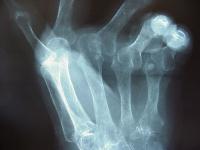

Clinical Example: Rheumatoid arthritis

rheumatoid hand